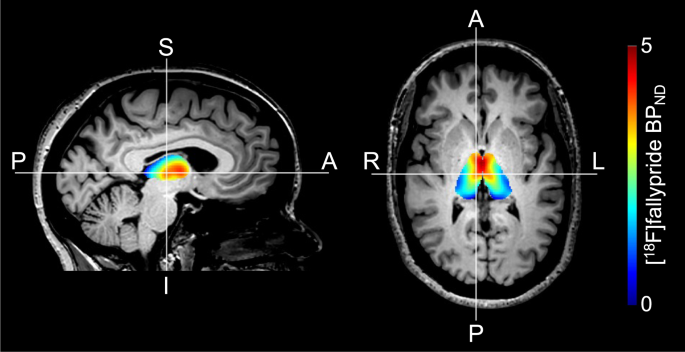

Figure 3 shows an example of the [18F]fallypride BPND values in the thalamus. Across all participants, we did not observe an association between thalamic ΔGABA and D2-like receptor availability, while adjusting for age (p = 0.973). However, we observed that this relationship appears to differ between ICB+ and ICB− patients (p = 0.051) (Fig. 4).

Previous studies of compulsive eating and hypersexuality have linked thalamic signaling to behavioral manifestations of appetitive motivation. For instance, differential GABA agonism in the paraventricular nucleus or medial dorsal nucleus of the thalamus can increase or suppress appetite45. Likewise, thalamic activation in response to sexual stimuli is greater in patients with hypersexual behavior46. We interpret the difference in DAA-induced thalamic GABA to emphasize a biological effect of this medication effect on the balance of the direct and indirect pathway activation. These pathways operate in a concert given their opposing effect on movement and behavior. The relative absence of a thalamic GABA response in patients with ICB suggests a greater direct pathway stimulation or blunted indirect pathway activation. Previous studies that employ optogenetic techniques in assessments of rodent behavior indicate that activation of direct pathway neurons in the ventral striatum (i.e., nucleus accumbens) induce a behavior similar to what is encountered in patients with ICBs39. These compulsive or persistent pursuits are of naturally rewarding behaviors (e.g., shopping, gambling, eating, and sex). We cannot rule out the possibility that the medication effect acts on thalamic dopamine receptors. We have previously described reduced D2-like receptors in the thalamus of PD patients47, but have not seen differences in patients with and without ICBs48. D2-like receptors in the thalamus are highly concentrated in the medial dorsal nucleus, and anterior nucleus49 (Fig. 3). As only a subset of the participants in the study (n = 20) underwent the PET scans, these results should be interpreted carefully with the expectation that a larger sample size may capture relationships not currently evident. These nuclei are important in modulating decision making and behavior, thus we speculate that the GABAergic response is localized here, hence the relation to behavioral symptoms in patients. The limitation of MRS is that we cannot provide accurate localization to specific nuclei of the thalamus. Furthermore, the lack of change in motor cortex GABA50, suggests that the medication effect may be localized subcortically, where future studies should assess striatal GABA changes in response to dopamine therapies.

A subset of 20 participants (10 ICB+ and 10 ICB−) completed a PET scan with [18F]Fallypride as described in refs. 47,48. D2-like receptor levels were estimated using the simplified reference tissue model (SRTM) performed in PMOD software version 3.7 (PMOD Technologies, Zurich Switzerland) to measure [18F]fallypride binding potential (BPND; the ratio of specifically bound [18F]fallypride to its nondisplaceable concentration as defined under equilibrium conditions)47,48. BPND images were co-registered to the T1-weighted image using FSL FLIRT (FSL v5.0.2.1, FMRIB, Oxford, UK). FSL FIRST was used to obtain the thalamic mask and the mean BPND values were recorded (Fig. 3).